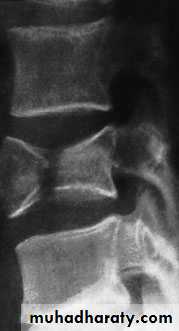

Flexion–compression injury

This is by far the most common vertebral fracture and is due to severe spinal flexion, though in osteoporotic occur with minimal trauma.

The posterior ligaments usually remain intact,

Pain may be quite severe but the fracture is usually stable.

Neurological injury is extremely rare.

Those with moderate wedging (loss of 20–40 per cent) of anterior vertebral height) and a stable injury can be allowed up after a week, wearing a thoracolumbar brace or a body cast applied with the back in extension.

If loss of anterior vertebral height is greater than 40

per cent, it is likely that the posterior ligaments have

been damaged by distraction and will be unable to

resist further collapse and deformity. If the patient is

neurologically intact, surgical correction and internal

fixation is the preferred treatment,